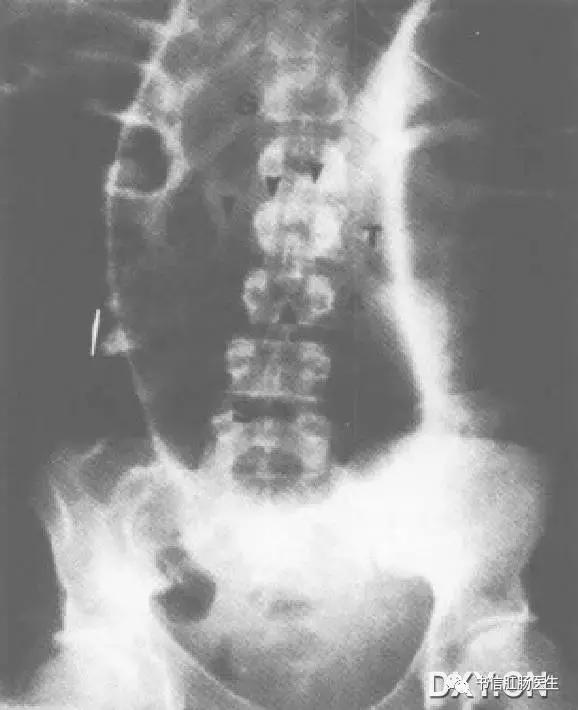

★ 男性,43 岁,乙状结肠扭转。仰卧位腹部 X 线平片显示明显扩张的乙状结肠(S)上缘到腹部最上方,横结肠(T)穿过扩张的乙状结肠(S),箭头为横结肠的下缘。

■ 影像表现:仰卧位腹部 X 线平片提示明显扩张的乙状结肠上升至腹部最上缘,位于横结肠的上方。

■ 征象解析:当患者仰卧时,肠腔内的气体聚集在横结肠,是结肠最靠近腹侧的一段。横结肠穿过正中线,把腹膜腔分为结肠系膜上、下半球。因此,横结肠被认为是腹部的赤道。正常情况下,乙状结肠被限制在南半球,尾部朝向横结肠(结肠系膜下)。在乙状结肠扭转时,可见乙状结肠的顶部向头侧移位或到赤道以北(结肠系膜上),称为朝北征。

■ 讨论:肠扭转是一段肠管沿其系膜长轴旋转而造成的闭襻性肠梗阻,肠系膜过长,系膜根部附着处过窄、过松或粘连、挛缩等为肠扭转发病的解剖因素。乙状结肠和附属的肠系膜必须围绕着至少一个固定点旋转,这种旋转引起闭襻性肠梗阻及不同程度的动静脉供血不足。早期诊断迅速减压,可以阻止肠管的缺血和穿孔。

乙状结肠扭转的典型 X 线表现:卧位腹片见乙状结肠极度扩张,其肠管内径多在 10 ~15 cm,甚至可达 20 cm 以上。肠皱襞因极度扩张而不能显示。扩大的乙状结肠弯曲呈马蹄形,马蹄的圆顶高达上腹或隔下两指向下直达盆腔,马蹄的中间为两肠内壁合并构成的直线形高密度影从中腹部直伸人盆腔,称集中线征。